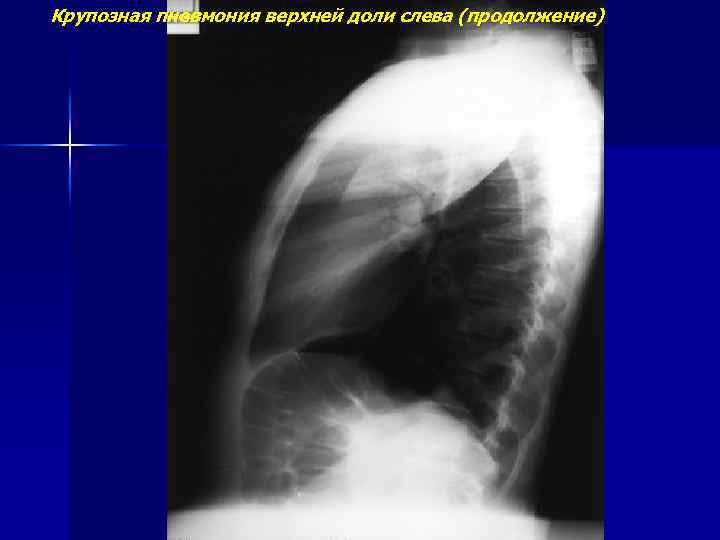

Крупозная пневмония верхней доли слева (продолжение)